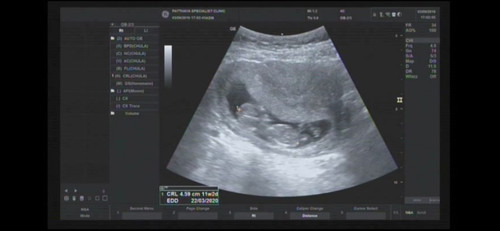

สวัสดีค่ะ ตอนนี้ท้องได้3เดือนจะเข้า4 แร้ว แม่ๆคนไหนตั้งครรภ์แร้วมีโรคไทรรอยร่วมด้วย เครียดมากกว่าน้องไม่แข็งแรง